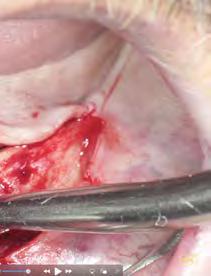

–Corticotomías y Ortodoncia. Ampliando límites del movimiento dental, por la Dra. Aranzazu Senosiain y cols. [50]

–Tratamiento de un caso de Ortodoncia y Cirugía Ortognática con placas preformadas y tecnología 3D, por la Dra. Elena Bonilla Morente y cols. [62]

–Uso del anclaje esqueletal como alternativa eficiente en el manejo ortopédico de clases III por deficiencia de maxilar superior, por el Dr. Carlos Becerra y cols. [74]

–MARPE, una alternativa a la disyunción en el paciente adulto, por el Dr. Enrique Solano y cols. [88]